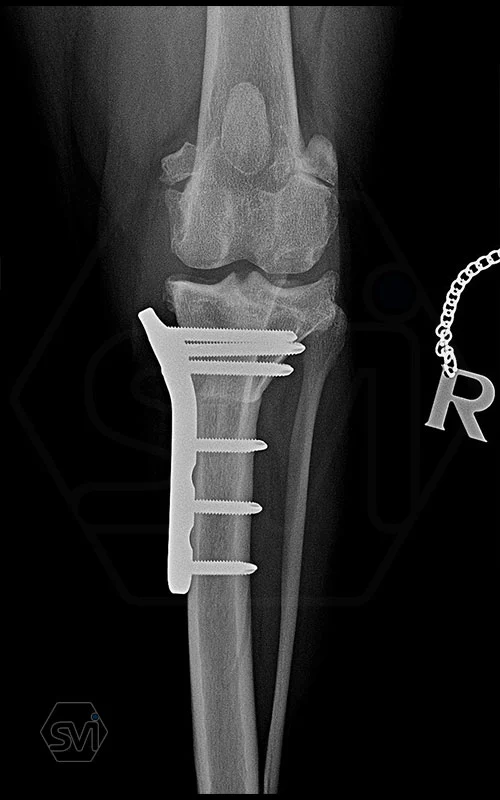

The NEW precontoured polyaxial locking TPLO plate family

One of the most important goals in the development of TPLO plates is, in addition to maximum stability, the simplest possible use, to facilitate the work of the surgeon, and to shorten the surgical time. Intraoperative modeling of plates often requires serious physical force, due to the deformation of the plate, weak points are formed in its material, which can lead to breakage of the plate or loss of lockig stability due to deformation of the holes. It can also lead to breakage of srews.

It is therefore advantageous to bend the plates in advance, conture them according to the anatomical shape, and then drill the holes. In most cases, the plates made in this way fit perfectly on the surface of the tibia, and the screws can be placed in the holes at the most optimal angle for maximum stability. Minor deviations in the fit of the plate to the bone surface do not need to be corrected for further intaraoperative curvature of the plate due to locking stability. And the polyaxiality allows you to choose the most optimal direction for inserting the screws.

The precontoured plates are designed so that using the monoaxial drill guide, all screws will be parallel to the plane of the tibial plateau, thus avoiding the screw being inserted into the joint and creating a screw-plate connection with maximum stability.